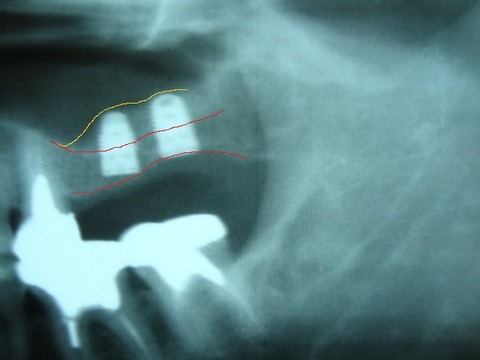

以下の写真は 先日 行ったソケットリフト症例です。

サイナスリフト症例となるべく 骨の薄い部分も存在する症例であります。

黄色の線で書いた上顎洞底の粘膜( シュナイダー膜)を破らないようにしてリフトアップさせます。

上顎骨とシュナイダー膜の間に インプラント体(フィクスチャー)と 骨補填材(将来 骨に置換され

るものです)を入れていきます。

バルーンリフトテクニックは使用しておりませんが、リフティングドリルと骨補填材の使用により、

全く患者様に負担の無い治療ができました。 治療時、治療後 共に殆ど痛みはなかった

ということでありました。